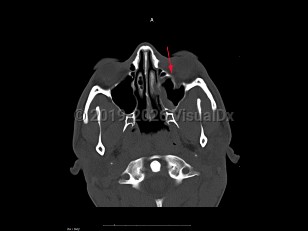

Blow-out fracture of orbit - External and Internal Eye

After sustaining a blunt force injury with an object larger in size than the globe, such as a fist or ball, the orbit is at risk of a "blow-out fracture." Although the lamina papyracea is the thinnest bone of the orbit, the orbital floor is the most common type of orbital fracture. This type of fracture tends to occur just behind the orbital rim but may involve the rim itself.

Patients often present with pain and tenderness to the periorbital region, which may worsen on attempted upgaze. They may note diplopia if there is limited motility of the involved eye. Signs of orbital floor blow-out fracture may include ecchymosis, enophthalmos, hypesthesia of the cheek, crepitus, and restricted eye movements, particularly in upgaze.

As the swelling decreases with time after the trauma, enophthalmos becomes more apparent in larger fractures. In many orbital fractures, swelling and ecchymosis are the only signs.